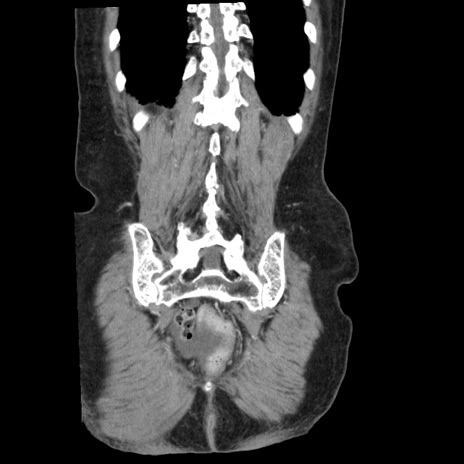

症例1(冠状断像)

【症例】80歳代女性

【主訴】腹痛

【現病歴】8時間前から腹痛あり来院。

【既往歴】糖尿病、脂質異常症、子宮体癌にて子宮全摘術

【身体所見】意識清明・会話良好だが腹痛で苦悶様、全腹部にわたって反跳痛と圧痛あり

【データ】WBC 13600、CRP 0.14、LDH 224、CK 90

矢状断像